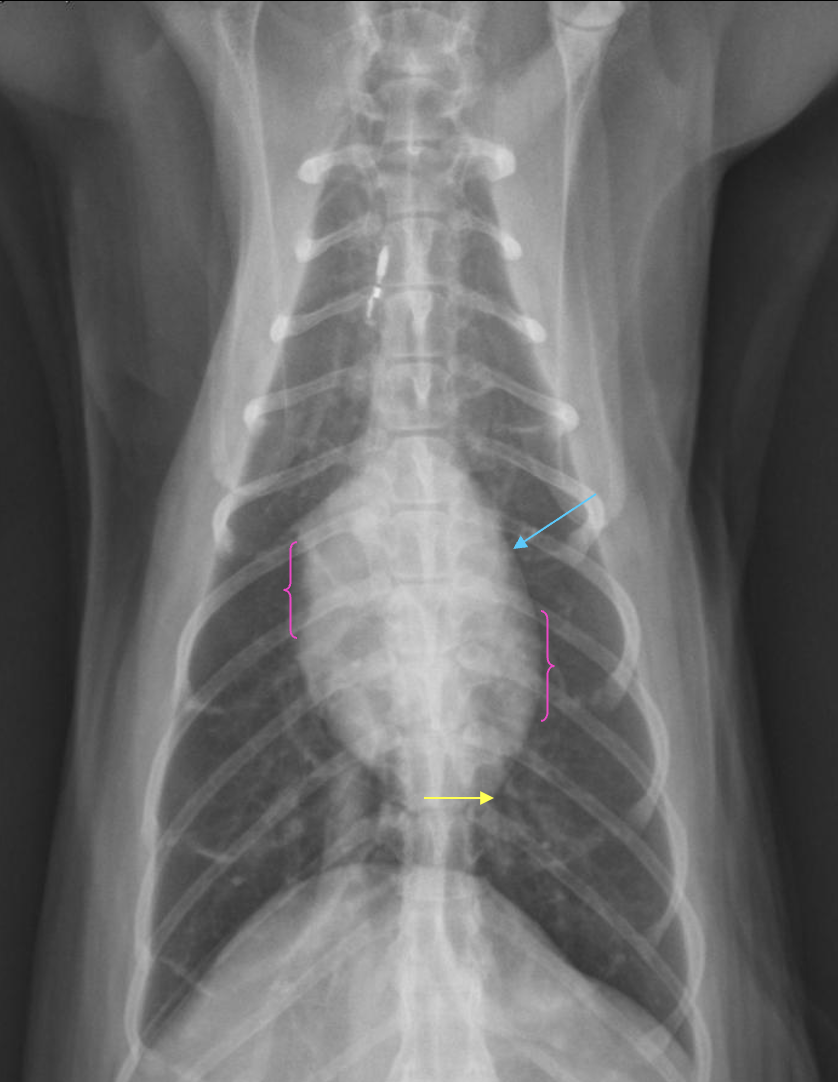

What is shown in these images?

generalized cardiomegaly